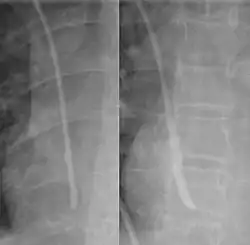

Luego, la línea se inserta usando la técnica de Seldinger: se pasa una guía roma a través de la aguja y luego se retira la aguja. Se puede introducir un dispositivo de dilatación sobre el alambre guía para aumentar el diámetro. Finalmente, la propia línea central se pasa por encima del alambre guía, que luego se retira. Se aspiran todos los lúmenes de la vía (para asegurarse de que estén colocados dentro de la vena) y se lavan con solución salina o heparina.[1] Posteriormente, se puede realizar una radiografía de tórax para confirmar que la vía está colocada dentro de la vena cava superior y que no se causó neumotórax accidentalmente. En radiografías anteroposteriores, una punta de catéter entre 55 y 29 mm por debajo del nivel de la carina se considera una ubicación aceptable.[33] El seguimiento electromagnético se puede utilizar para verificar la ubicación de la punta y proporcionar una guía durante la inserción, evitando la necesidad de rayos X posteriormente.

Un catéter venoso central fijado a la piel con sutura. -

Radiografía de tórax con catéter en vena subclavia derecha -

El contorno de la vena cava superior en una radiografía de tórax está etiquetado a la izquierda.